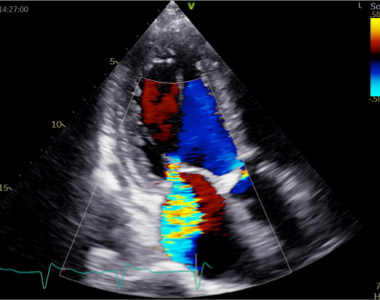

弁膜症の診断は、自覚症状が重要です。診察では、動悸・息切れ・疲れやすさなど、どの程度日常生活が制限されているかを問診します。さらに視診・触診を行って呼吸の状態や浮腫の有無を判断し、聴診により心雑音の有無と性状を確認します。弁膜症の検査は、胸部レントゲン写真・心電図・血液検査なども行いますが、なんといっても心エコー図検査は診断的価値が高いです。

心エコー図検査は体に害のない、痛みを伴わない検査です。どの弁が障害されているのかを特定し、その動きや狭窄・逆流の程度を診断します。同時に、心臓の部屋の大きさや機能を診断しますが、これらは治療方針に直結します。体に負担のない検査なので、治療後に繰り返し検査をして、どの程度改善しているかを評価することもできます。さらに、手術が必要な方には、心臓血管外科医が手術を行う際に必要となる様々な情報を提供します。

心エコー図検査